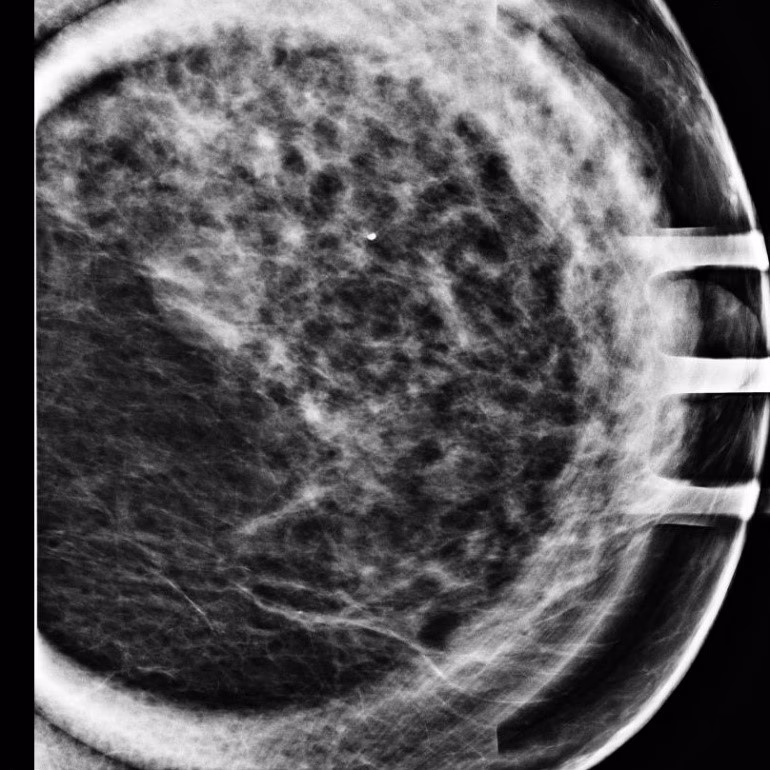

Your doctor can provide personalised recommendations based on your individual health profile, medical history, and any existing medications. They can ensure that EPO is compatible with your current treatments and will not interact adversely. If you present with a breast lump or suspicious tissue, your doctor will likely recommend diagnostic tests such as a clinical breast exam, diagnostic mammogram, ultrasound, or even a breast biopsy to accurately assess the situation. Early diagnosis is key for many breast conditions, so never delay seeking professional medical advice for concerning symptoms.